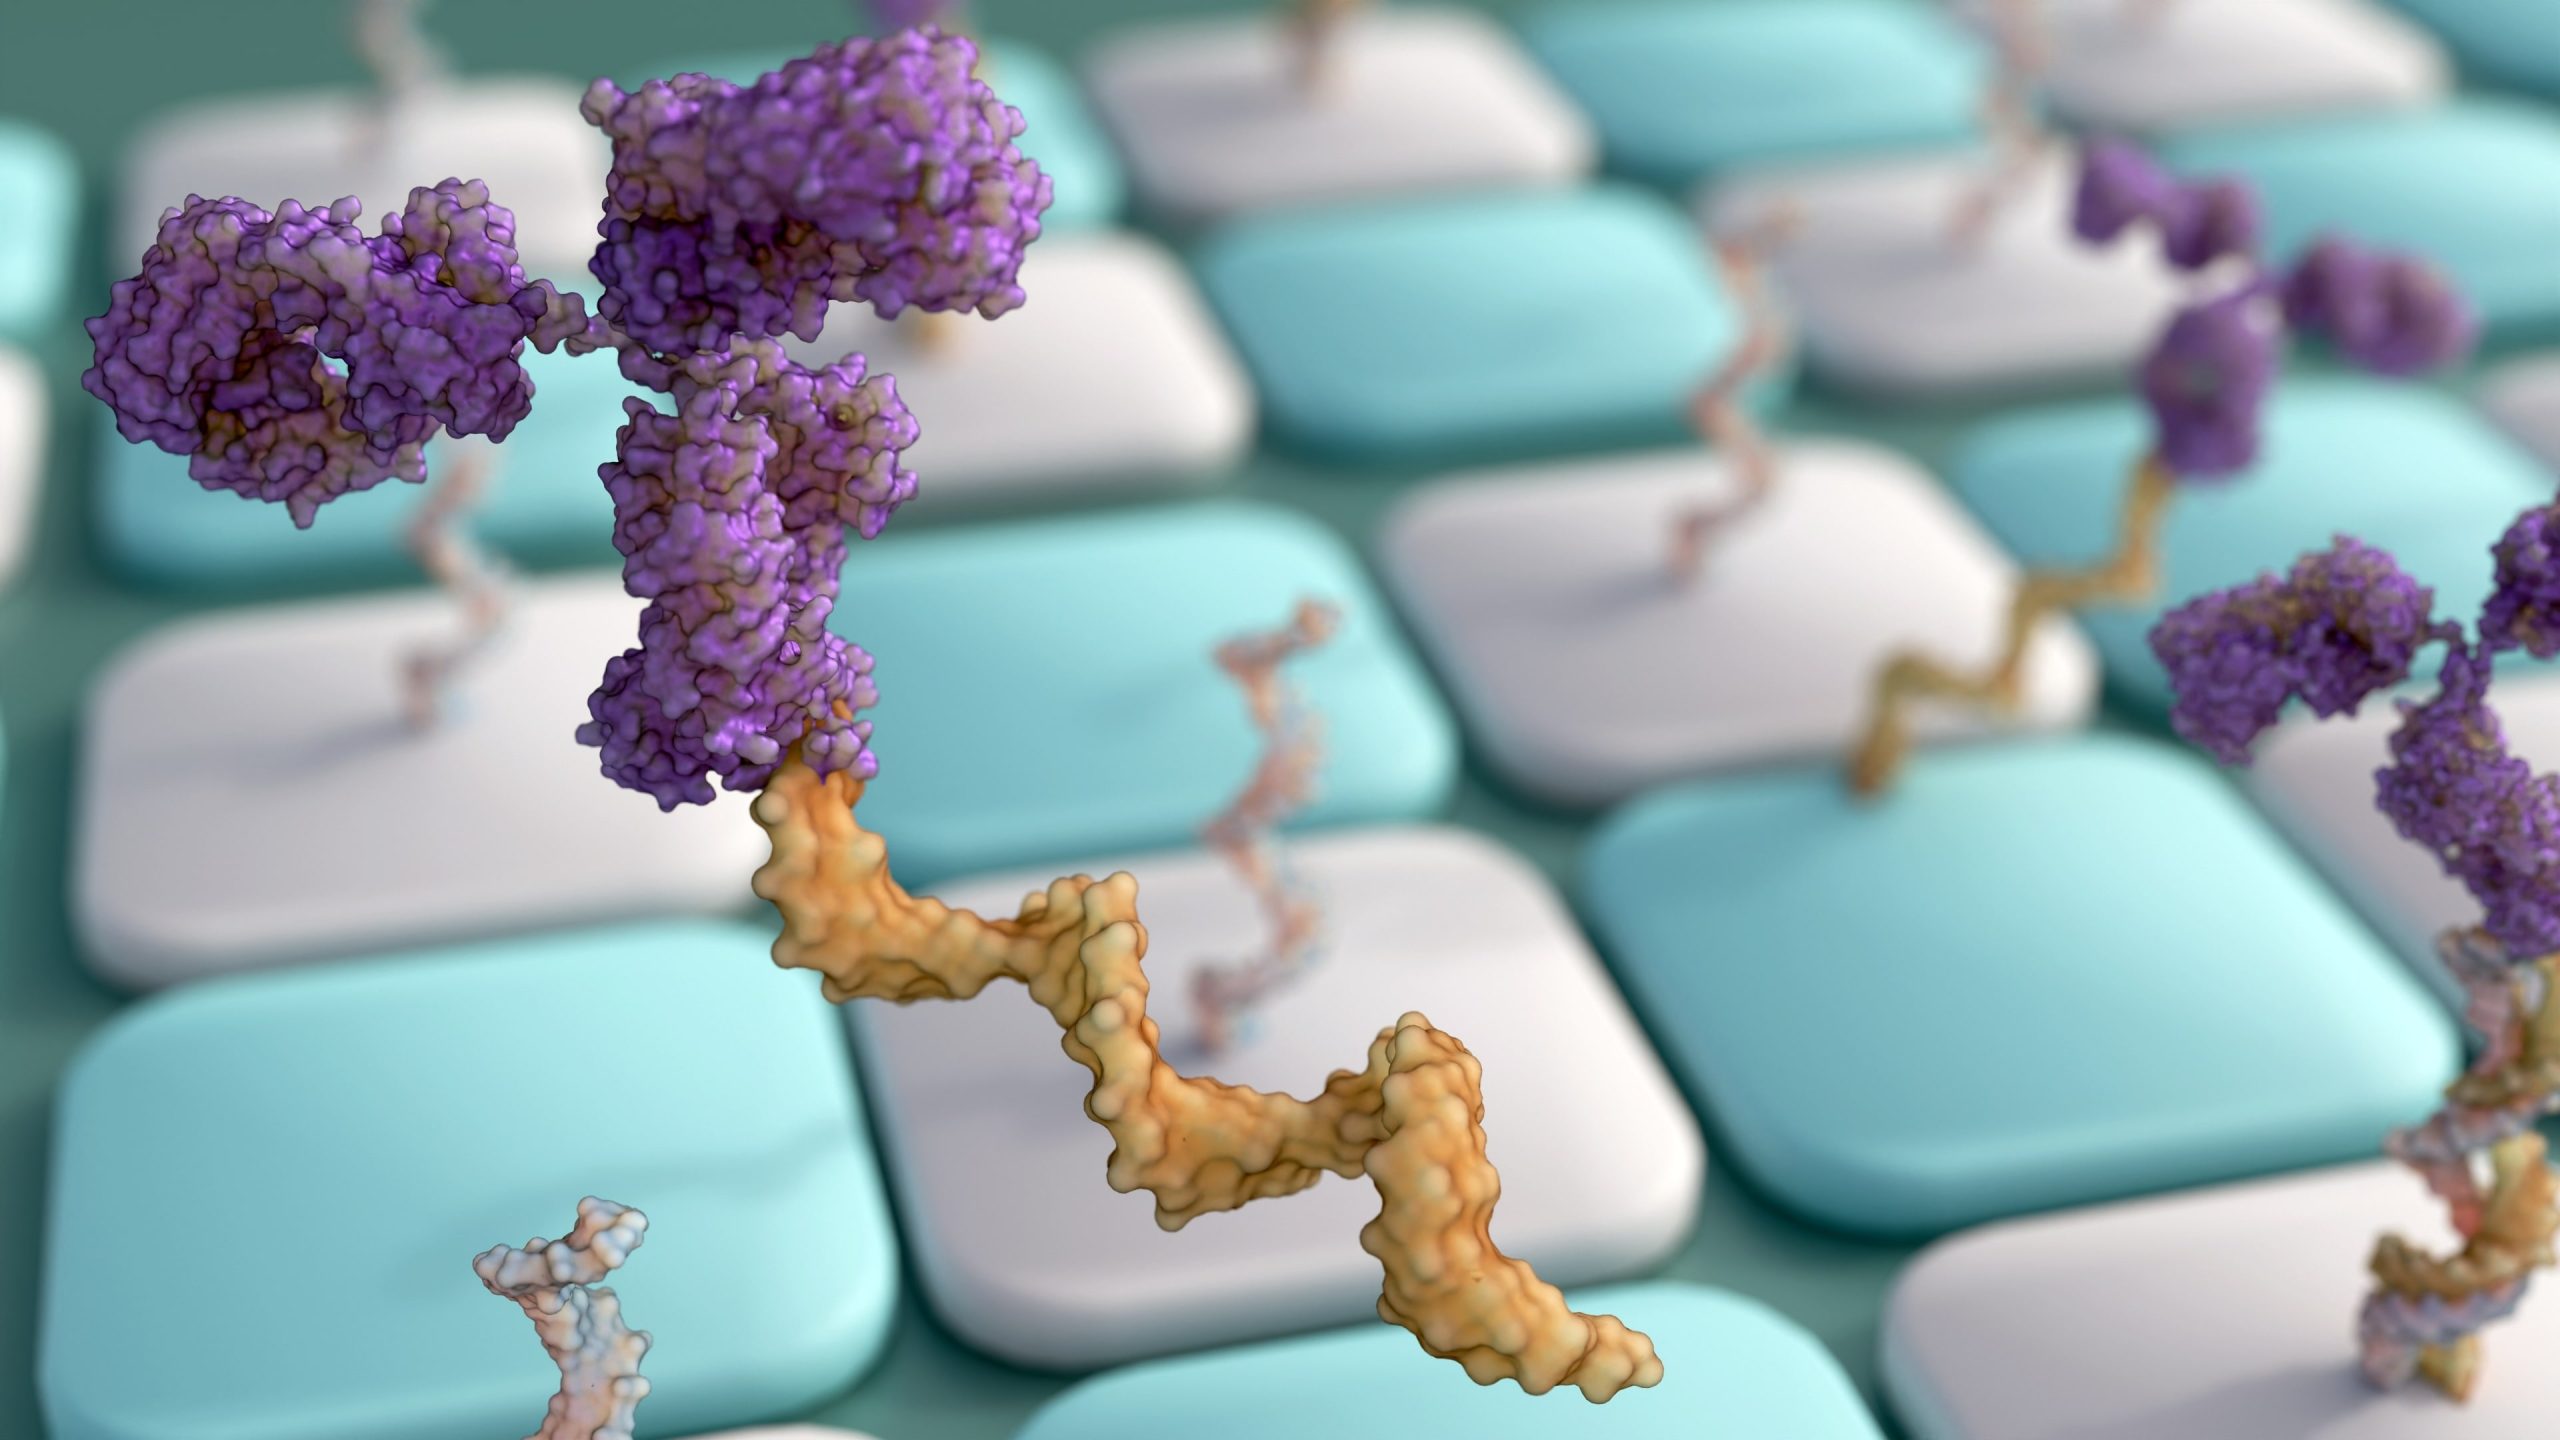

SOD1 protein found to trigger treatable Parkinson’s progression

Scientists at the University of Sydney have discovered a malfunctioning brain protein linked to Parkinson’s - which could lead to new therapies for the debilitating condition in the future.